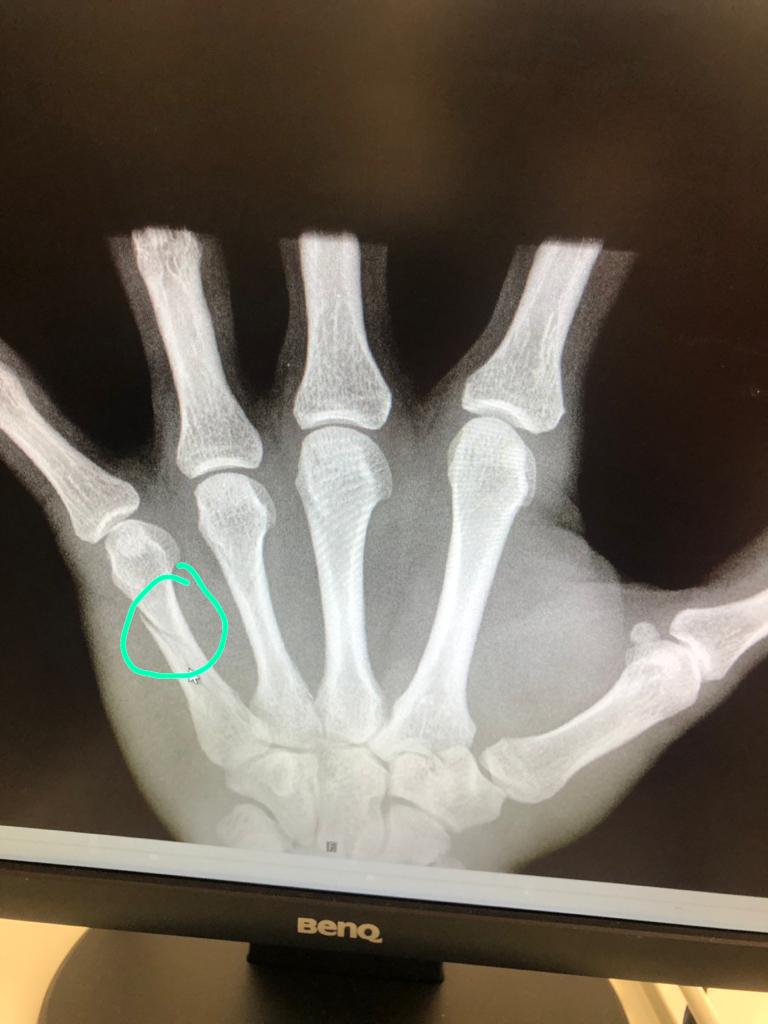

Спицов был доставлен в клинику доктора Doktor Johannes Huber from Kempten. По итогу осмотра и выполнения рентгенографии диагностирован перелом 5 пястной кости левой руки.

Так же в онлайн режиме проведен медицинский консилиум между медицинским штабом спортивной сборной команды Российской Федерации по лыжным гонкам и Калантырской Валентиной Анатольевной руководителем центра микрохирургии кисти, реконструктивной и пластической хирургии, к.м.н., доцентом кафедры травматологии и ортопедии РНИМУ им. Пирогова в АНО ЦКБ Святителя Алексия Митрополита Московского.

В ближайшее время Денис Спицов вернется в Россию для прохождения лечения.

Сроки восстановления до 6 недель.